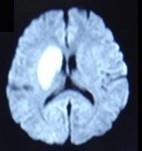

问题 男性,65岁,有高血压病史5年,因左侧肢体无力1天入院摔, 行头颅MRI出现如图所示病变,应诊断为 ( )

选项 A、硬膜下出血 B、脑出血 C、蛛网膜下隙出血 D、脑梗死 E、多发性腔梗 一、单项选择题

答案 D